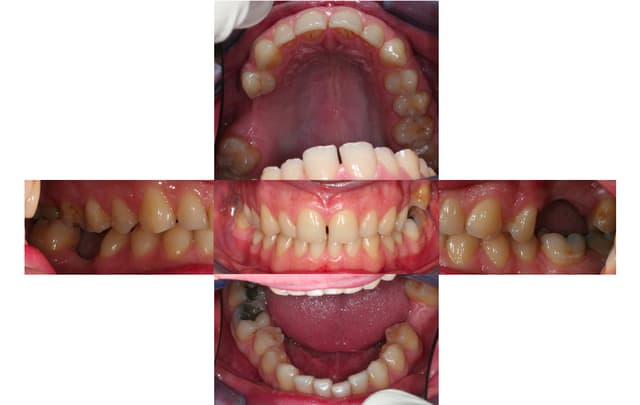

Bon je m'y colle, c'est pas le même niveau qu'olivier, mais ce sujet étant censé être pour les débutants je poste.

Patient 26 ans, à qui il manque 46, 25 et 26.

Pour l'instant je vous propose la partie préparation et mise en place de l'implant en 46, la suite peut être bientôt.

Dans l'ordre si le site veut bien, wax-up ( cirage pour céramik ;) ) , guide radio, et scan.

Photos pré-op, indicateur de direction en place et post-op.

Il s'agit d'un implant astra osseospeed de 5 mm de diamètre et 9 de long.

Prothèse prévue à 6 semaines.